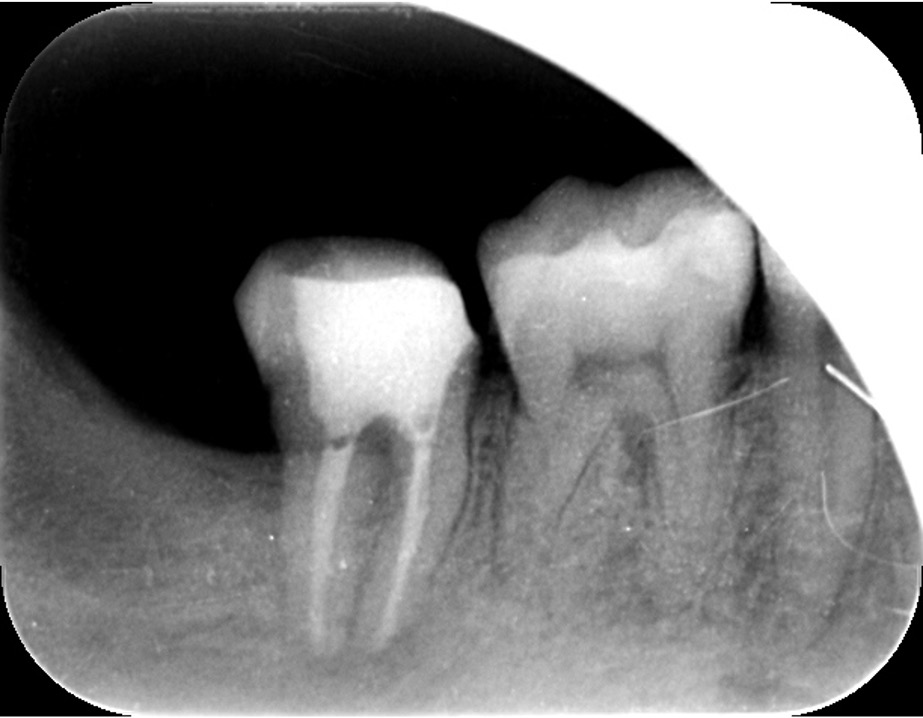

歯の根の治療は難しいことは先述しましたが、歯の内部からの治療だけでは治らないことがあります。

それは歯の先に枝分かれが多く存在し、そこにばい菌が入り込んで難治性となっているからです。ではその場合どうするのか?外科治療をします。その枝分かれの部分を切り落とすのです。今回はその前後のレントゲンの写真をお見せします。

| 根の中の薬が十分に充填されておらず、根の先が周りと比べて黒くなっており、炎症があると判断できます。 | 根の中にしっかりとお薬を緊密に充填しましたが、まだ根の先に黒くなっている部分があります。 |

このように外科的治療で病変部を切除することでしっかりと治癒させることが可能です。根の治療は細菌との戦いです。難しいですが、やりがいがあります。